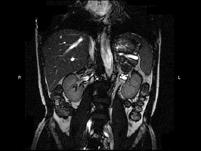

问题 男,52岁,下肢无力伴多饮多尿2?年余,实验室检查:低血钾,血醛固酮水平及24小时尿醛固酮定量超过正常值,MRI检查如图所示,应诊断为()

选项 A.左肾上腺囊肿 B.左肾上腺腺瘤 C.左肾上腺嗜铬细胞瘤 D.左肾上腺髓脂瘤 E.左肾上腺转移瘤

答案 B